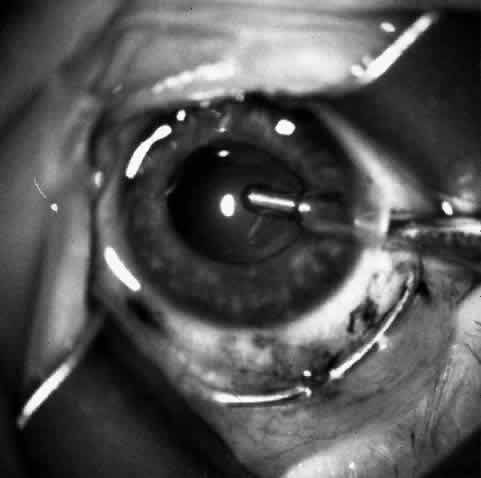

Sixteen to 22 interrupted 10-0 nylon sutures are placed to secure the edge of the lens in the peripheral corneal stroma trough. The first eight sutures are placed with the edge of the lens lying over the circular trephine mark (Fig. 10). As with any corneal transplant surgery, the second suture is the most important in centering the lens. All knots must be tied in such a way that the knots may be buried easily. At the same time, the sutures must not be tightened so tightly that compression occurs with the lens. My personal preference is for a 2-1-1 surgeon's knot. Care should be taken to prevent the lens from being sewn eccentrically into the bed, to prevent astigmatism. After the first eight sutures are placed, the edge of the lens is tucked into the stromal bed all around (Fig. 11) and the remaining 8 to 14 sutures are placed to fasten the lens securely in place (Fig. 12). The sutures are rotated so that the knots are buried in the recipient cornea. This allows the surgeon to remove the sutures at a subsequent examination under anesthesia (EUA) by means of traction directed peripherally without dehiscence of the wound.

Fig. 10. Lenticule is sutured with interrupted 10-0 nylon sutures.

Fig. 11. After the first eight sutures are in place, the edges of the lenticule are tucked into the bed.

Fig. 12. The remaining eight sutures are placed with the lenticule edges tucked.